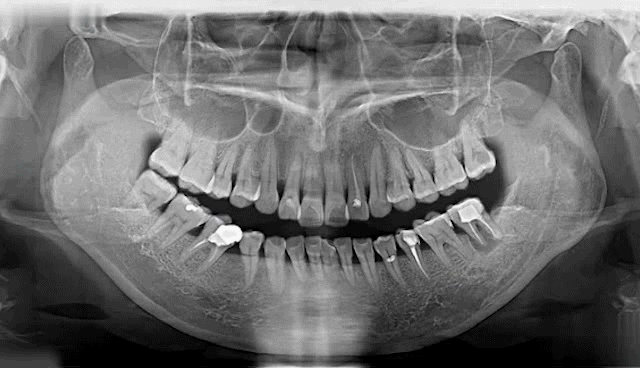

中华医学会调查结果显示:我国45岁以上中老年人79%存在缺牙现象,超过90%以上公民有牙齿不齐、龋齿、牙周病口腔问题,其中12岁儿童的恒牙患龋概率达到29%,牙颌畸形发病率恒牙期为72.92%,70岁以上的老年人许多都处在缺牙甚至无牙状态。